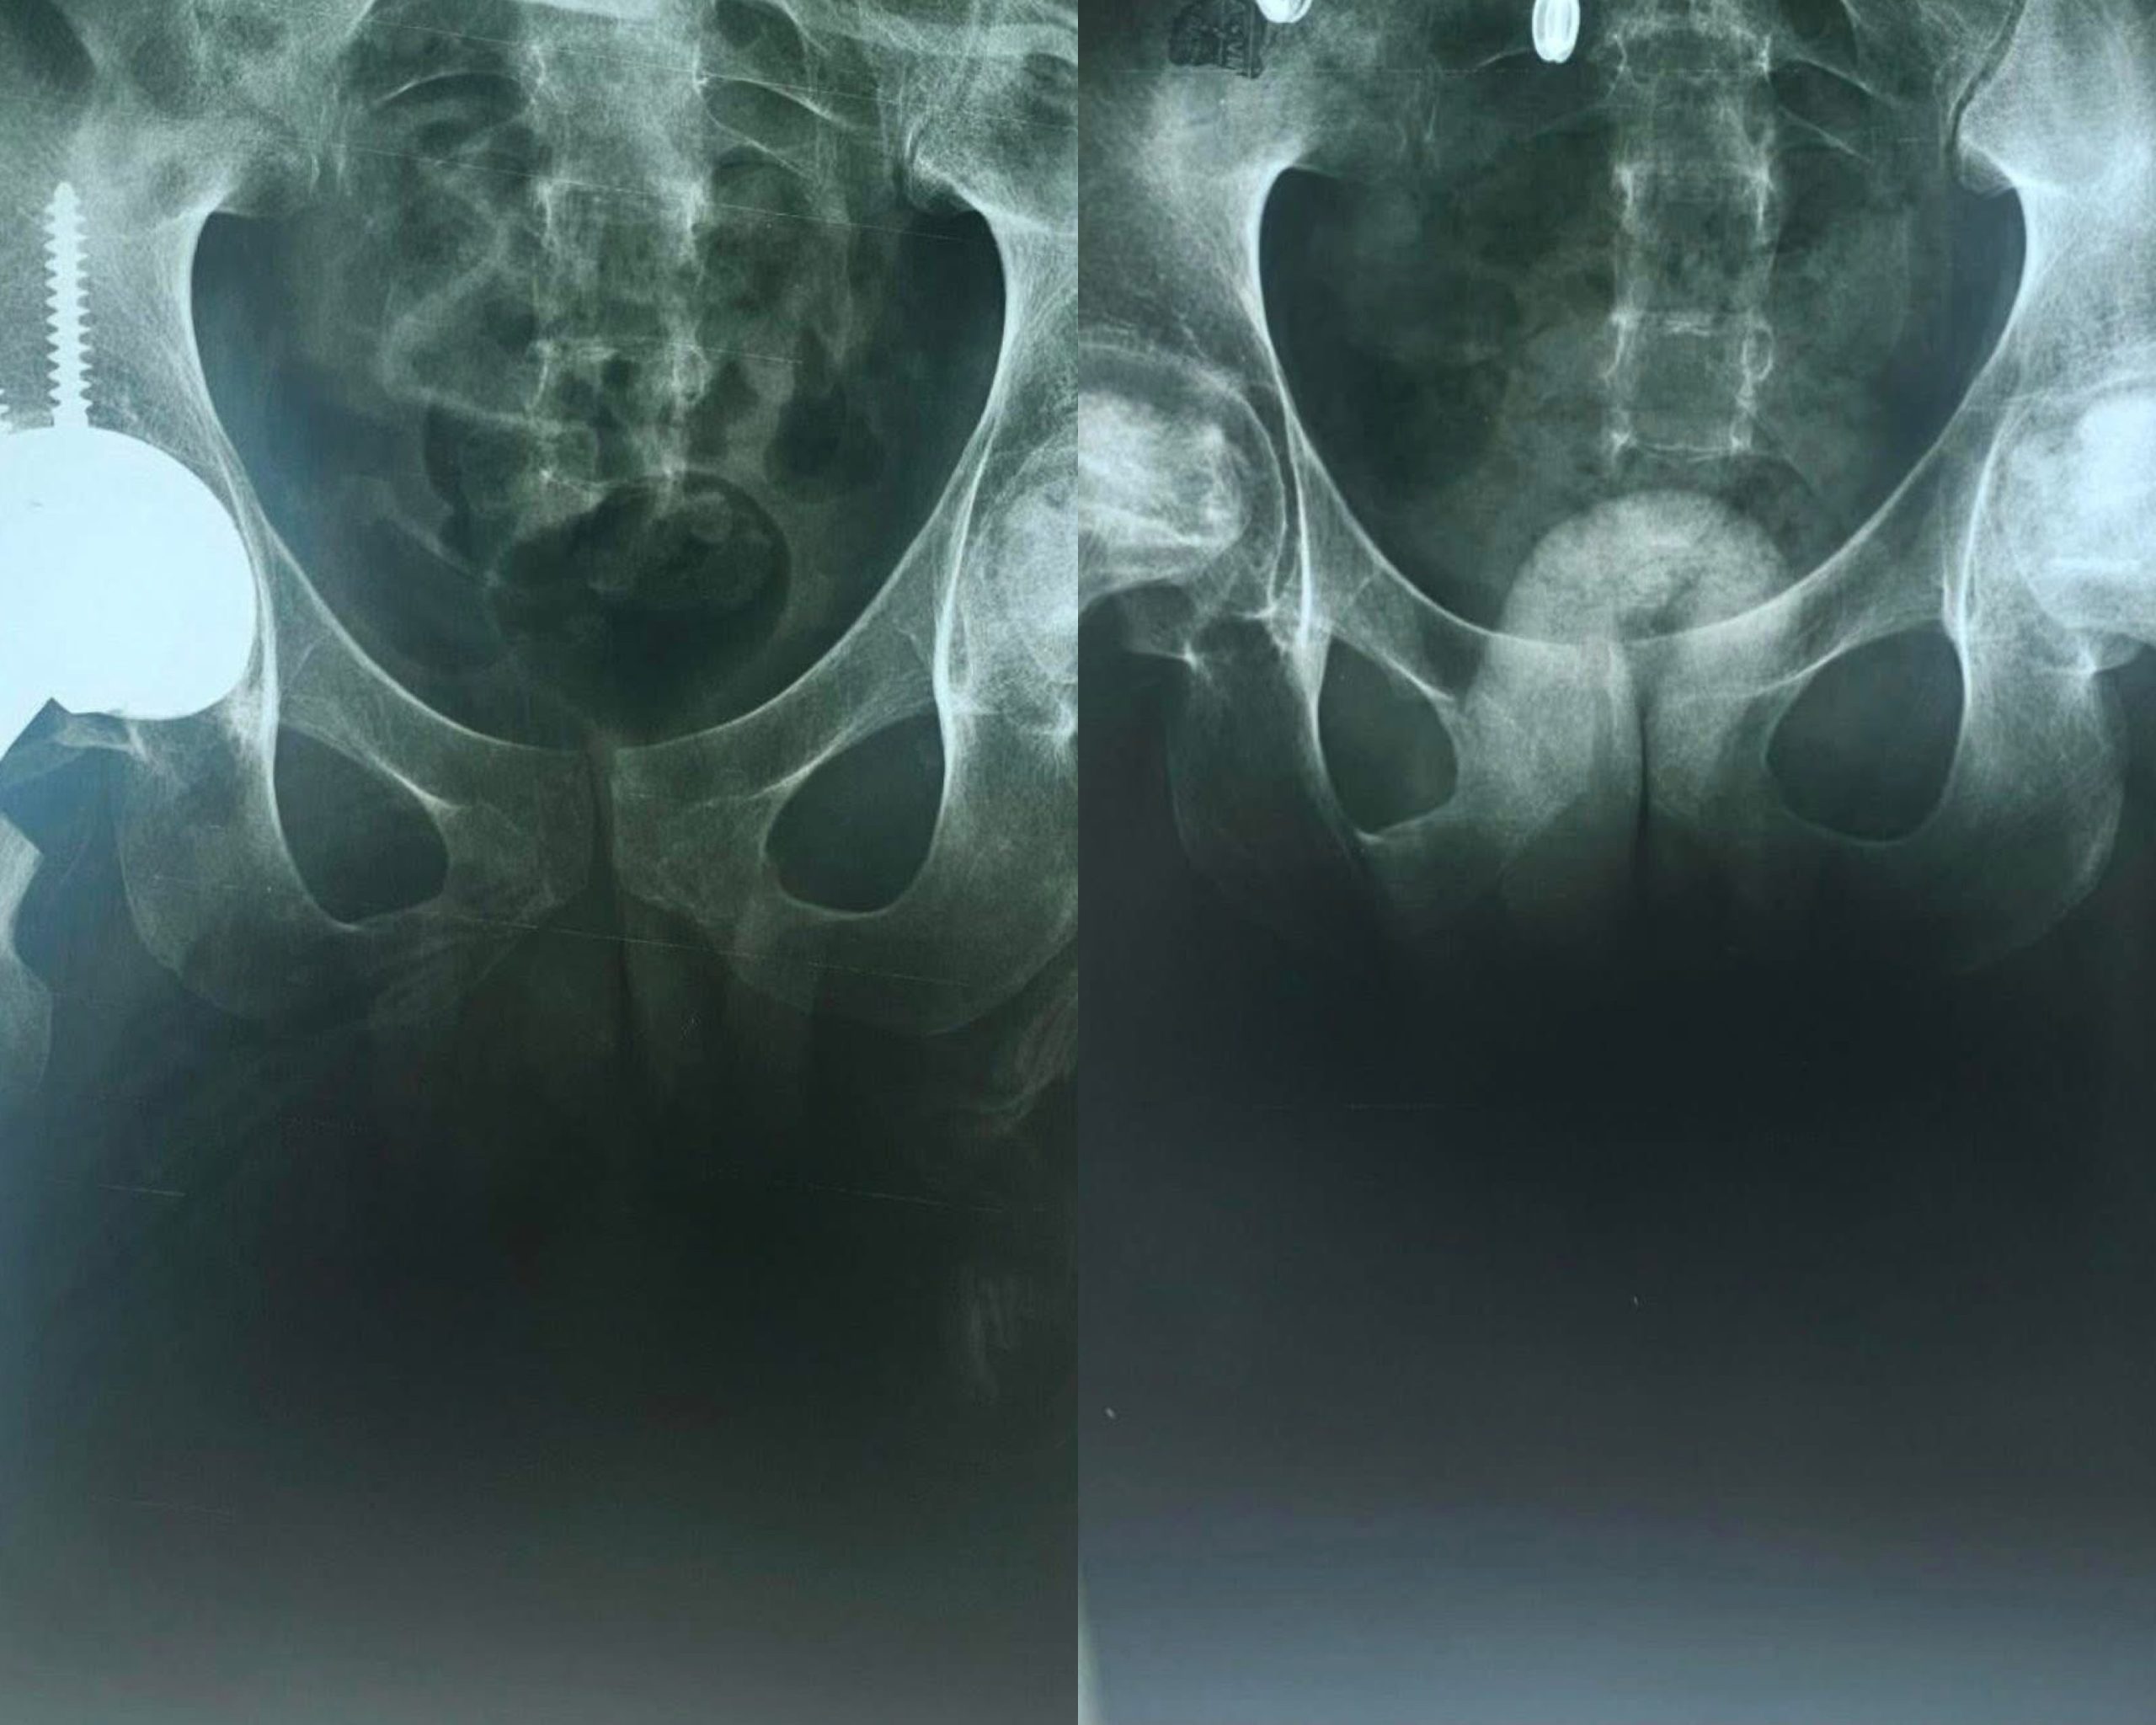

Пациент на 22-годишна возраст со дијагноза на акутна лимфоцитна леукемија и претходно подложен на алогена трансплантација на хематопоетски матични клетки пред една година, развил аваскуларна некроза на колковите, која се манифестира со силни болки и ограничено движење. Истиот успешно е опериран во нашата болница од страна на ортопедскиот тим во состав од прим. д-р Томислав Петровски, д-р Атанас Поп-Стефанија, д-р Михаил Чачор, и анестезиолог д-р. Александар Веслиевски, информираат од Болницата.

За време на операцијата, посочуваат, вградена е тотална ендопротеза на десниот колк со керамички компоненти.